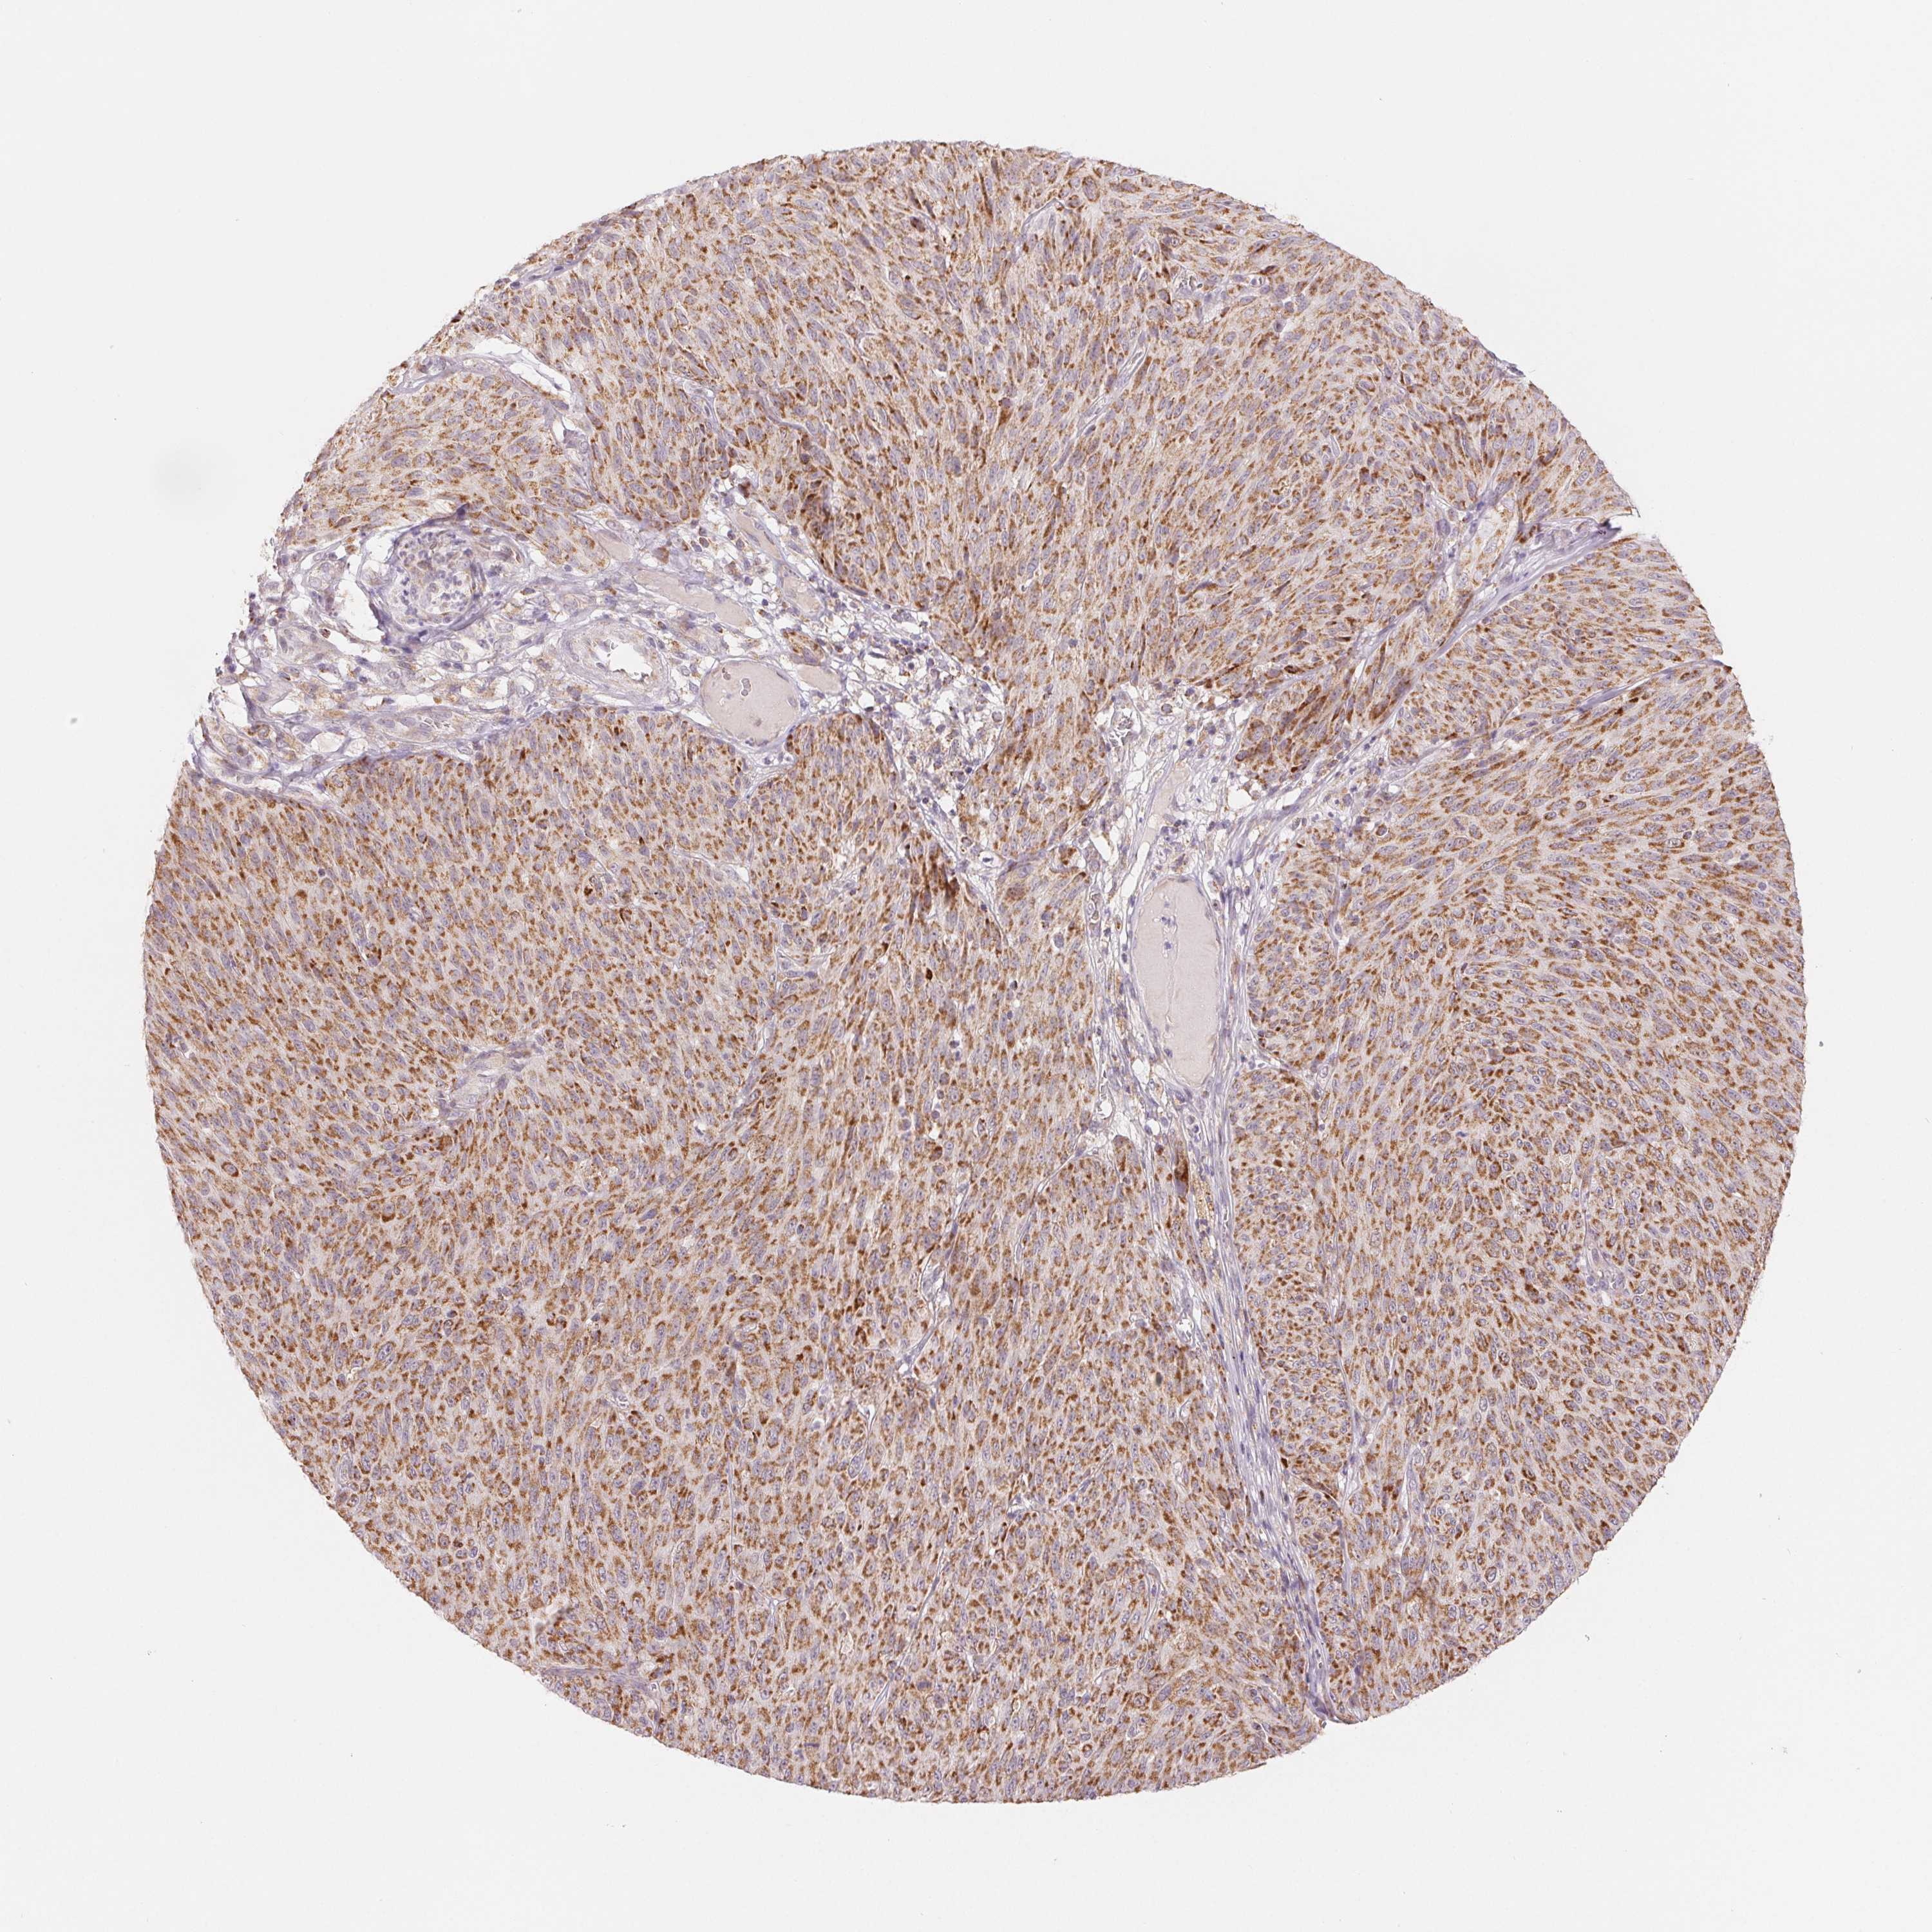

MELANOMA - Protein expressioni

A mouse-over function shows sample information and annotation data. Click on an image to view it in a full screen mode. Samples can be filtered based on level of antibody staining by selecting one or several of the following categories: high, medium, low and not detected. The assay and annotation is described here.

Note that samples used for immunohistochemistry by the Human Protein Atlas do not correspond to samples in the TCGA dataset.

Antibody stainingi

Antibody staining in the annotated cell types in the current human tissue is reported as not detected, low, medium, or high, based on conventional immunohistochemistry profiling in selected tissues. This score is based on the combination of the staining intensity and fraction of stained cells.

Each image is clickable and will lead to virtual microscopy that enables deeper exploration of all samples and also displays staining intensity scores, fraction scores and subcellular localization as well as patient and tissue information for each sample.

Antibody HPA020961

Antibody HPA059109

Staining

High

Medium

Low

Not detected

Intensity

Strong

Moderate

Weak

Negative

Quantity

>75%

75%-25%

<25%

None

Location

Nuclear

Cytoplasmic/membranous

Cytoplasmic/membranous,nuclear

Malignant melanoma, NOS

Malignant melanoma, Metastatic site